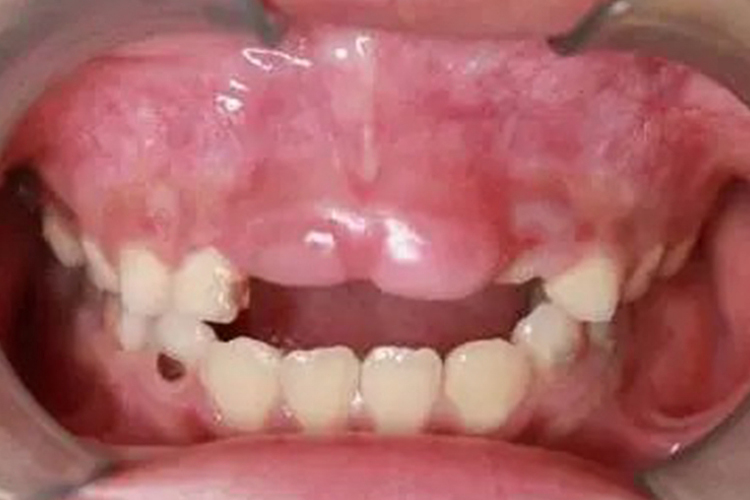

颅骨锁骨发育不全综合征以颅缝闭合延迟及锁骨发育形成不全为主要特征,常伴有半椎体及脊柱侧弯。外貌特征有出牙不足或乳牙持续生长,鼻根下限扁平,两眼距离增宽,眉弓高,前额膨隆,二肩下垂。此外,X线可示颅缝增宽,囟门增大,锁骨完全或部分缺如。